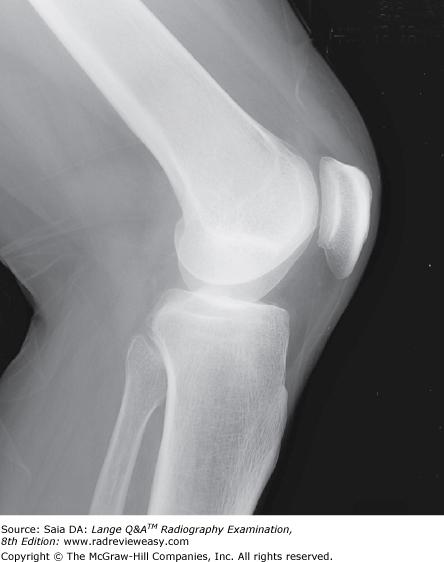

Which of the following statements regarding the radiograph in Figure A is (are) true?

1. The tibial eminences are well visualized.

2. The intercondyloid fossa is demonstrated between the femoral condyles.

3. The femorotibial articulation is well demonstrated.

1 and 3 only

In a lateral projection of the normal knee, the

- fibular head should be somewhat superimposed on the proximal tibia.

- patellofemoral joint should be visualized.

- femoral condyles should be superimposed.

1, 2, and 3

The mediolateral projection of the knee shown in Figure 6–1 could best be improved by

angling the CR about 5 degrees cephalad